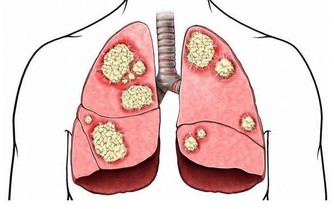

6、肝硬化腹水形成

肝硬化晚期腹水出現前常有腹脹,大量水使腹部膨隆,腹壁繃緊發高亮,狀如蛙腹,患者行走困難,有時膈顯著抬高,出現呼吸和臍疝。